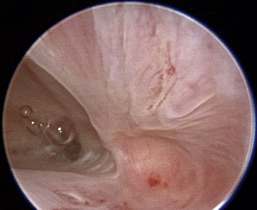

Normal turbinates have a smooth, pink-to-white surface and a spatial alignment that provides channels for the passage of air. The color varies and appears tan in the caudal nasal cavity. Turbinates come in different shapes and sizes, but the surface should be smooth. Ethmoid turbinates in the caudal nasal cavity will have a characteristic stippled or corrugated appearance (Figures 19-13 through 19-16). Ulcerations or various proliferations of the mucosa are indicative of disease. These changes are typically diffuse and accompanied by a lot of mucus. Mucus can be thin to purulent. Copious amounts can be flushed out of the nasal cavity to allow better visibility. The specific disease is determined by biopsy. After full examination of the nasal cavity, run the scope along the floor of the nasal sinus to the level of the choanae. Keeping the scope pointed in a ventral medial direction prevents inadvertent trauma or penetration of the cribriform plate. The index finger of the free hand can be used to follow the scope as it moves caudally over the hard palate; the surgeon can then palpate the scope through the soft palate when it moves into the nasopharynx. Some force is needed to complete this procedure and may result in increased bleeding.

image

Figure 19-13 Normal canine rostral nasal cavity; the septum is medial (left).